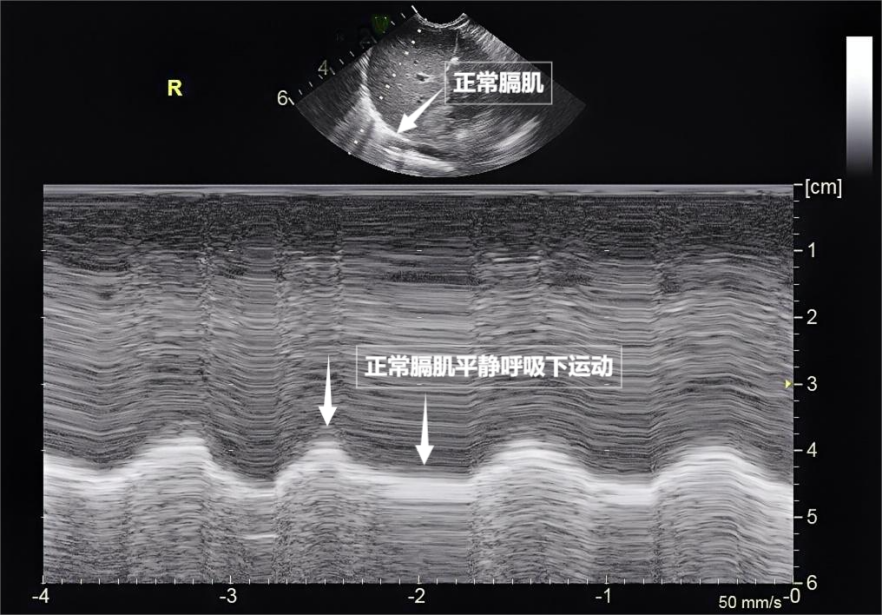

第三景:“呼吸的动力泵”的协同作战——呼吸肌肉

呼吸看似简单,实则是多组肌肉精密配合的“团体操”。肺部超声不仅能观察肺的形态,更能通过实时动态影像,“捕捉”这些呼吸肌的活动状态,为评估呼吸功能提供独特视角。膈肌是呼吸肌的“总指挥”,位于胸腔与腹腔之间。平静呼吸时,膈肌收缩下沉,胸腔容积扩大,空气自然吸入;舒张时,膈肌回升,肺部弹性回缩完成呼气。超声下可见膈肌呈光滑弧形,随呼吸规律上下移动(见下图)。肋间外肌则是“肋间隙的升降机”,收缩时上提肋骨,扩大胸腔前后径,辅助吸气。这对“黄金搭档”承担了日常呼吸70%以上的工作量,是维持呼吸的“主力军”。

图为正常膈肌超声表现